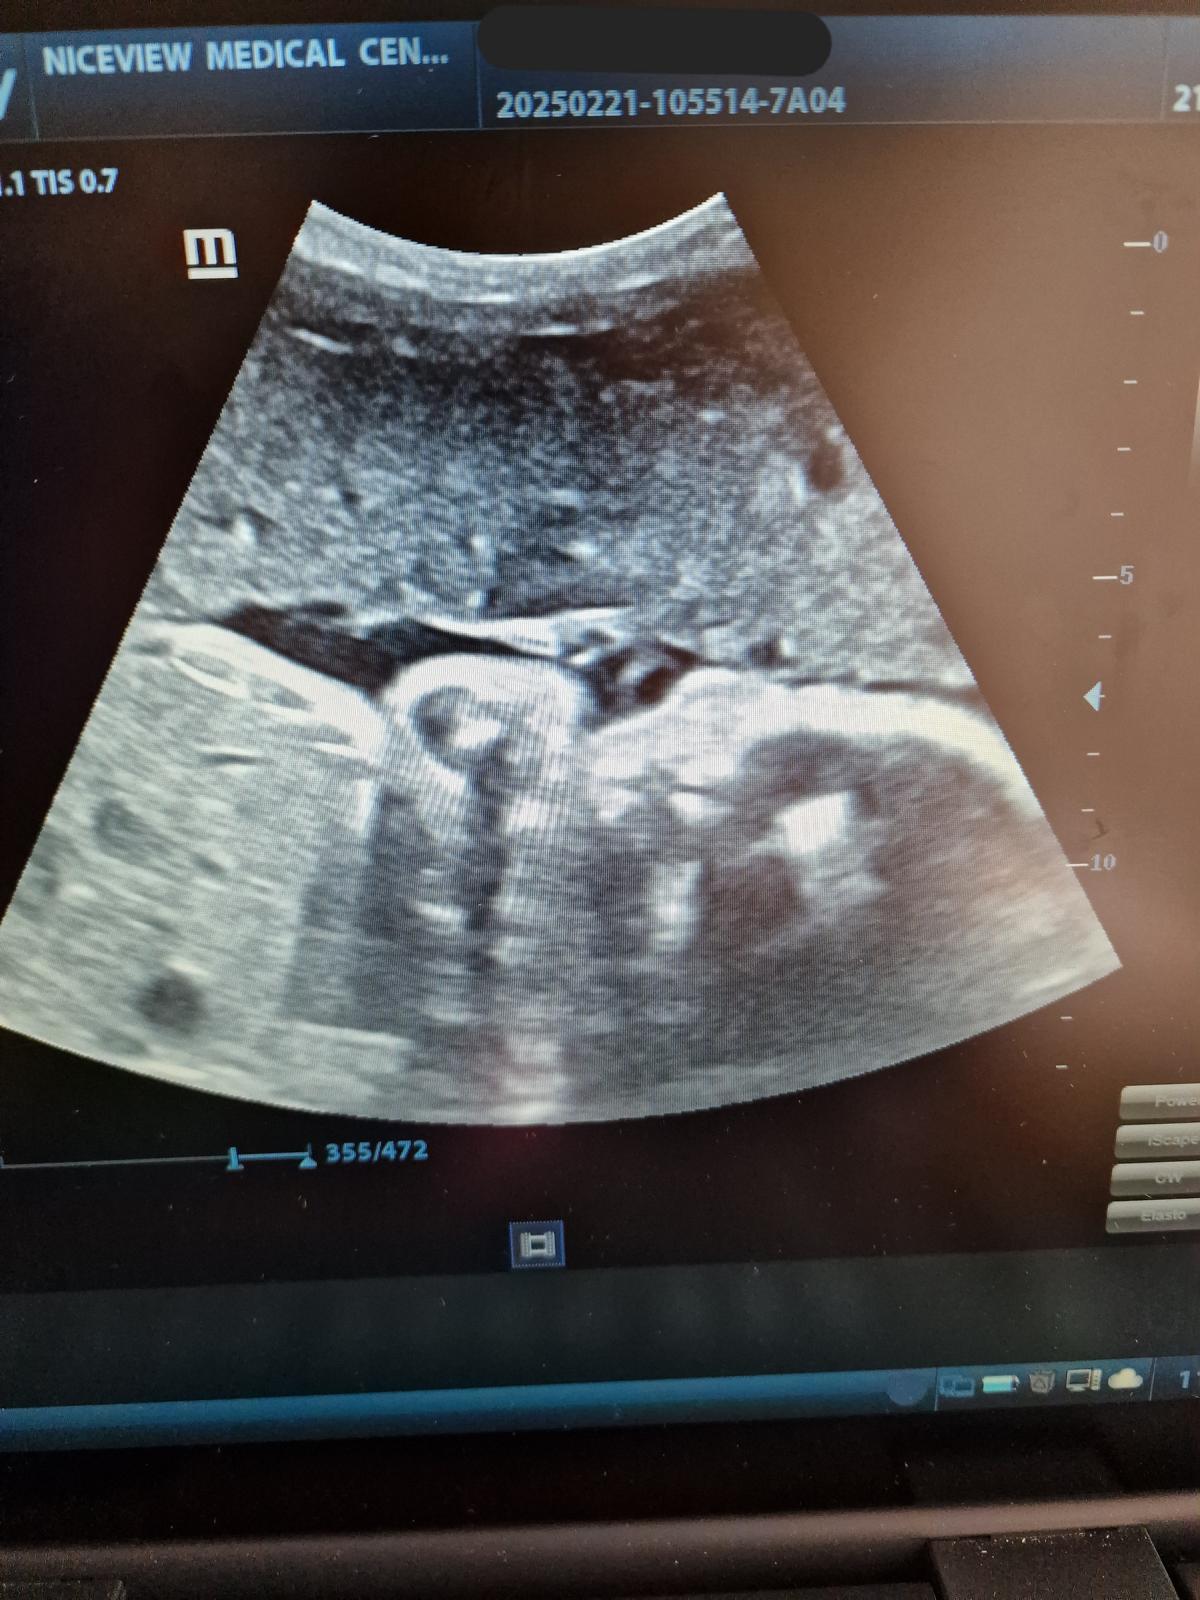

14. April 2025Von Herzen bedanken wir uns bei allen Förderern und Freunden, die es, auch Dank zusätzlicher Spenden, möglich gemacht haben. So kann die Schwangerschaftsvorsorge wieder wie gewohnt angeboten werden. Ebenso Herzecho und Doppler-Utraschall-Untersuchungen.

Die Bilder und das Dankesvideo, welche uns aus Kenia erreicht haben, teilen wir gerne mit euch.